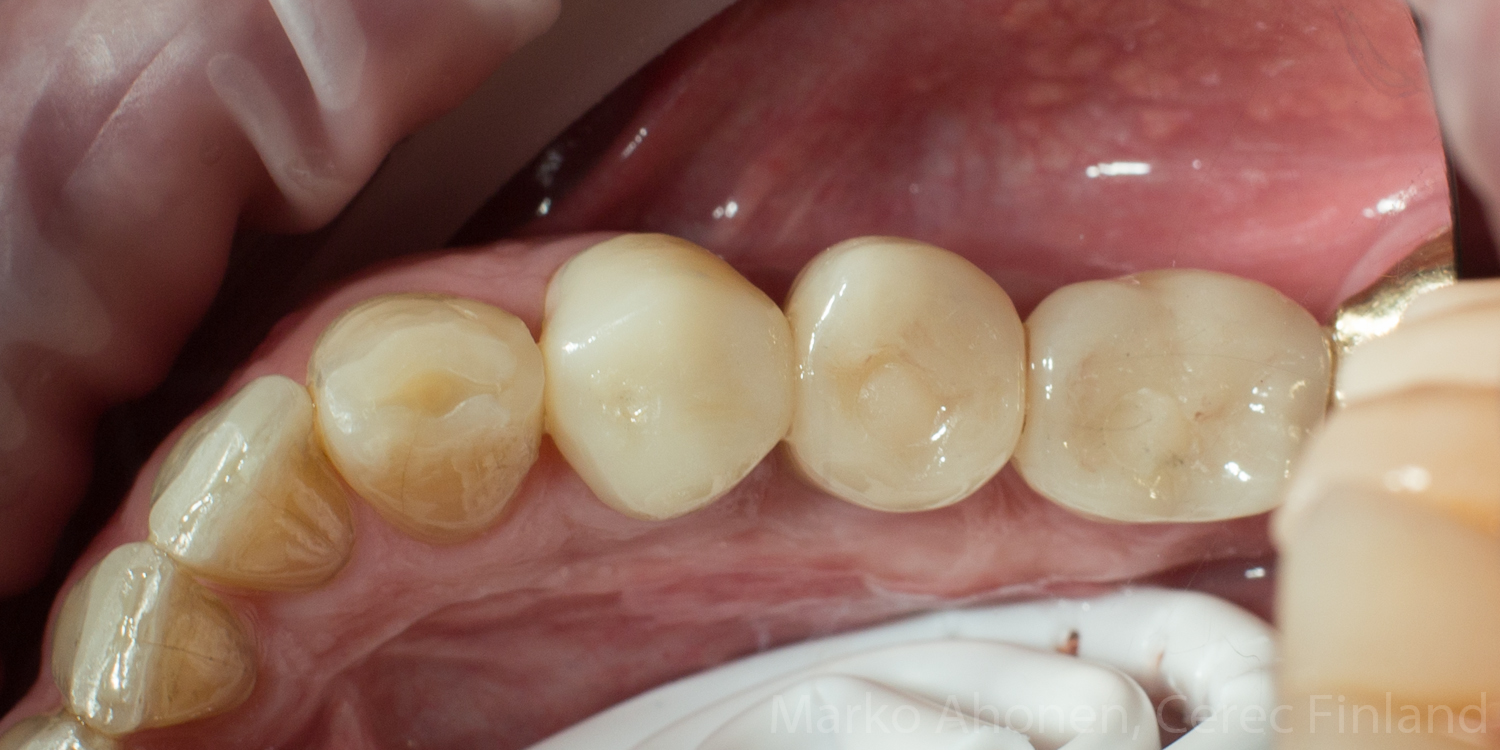

Valmiit implantit ja kruunu suussa (kontrolli 1kk hoidosta):

IMG_6352 IMG_6343 IMG_6349 IMG_6358